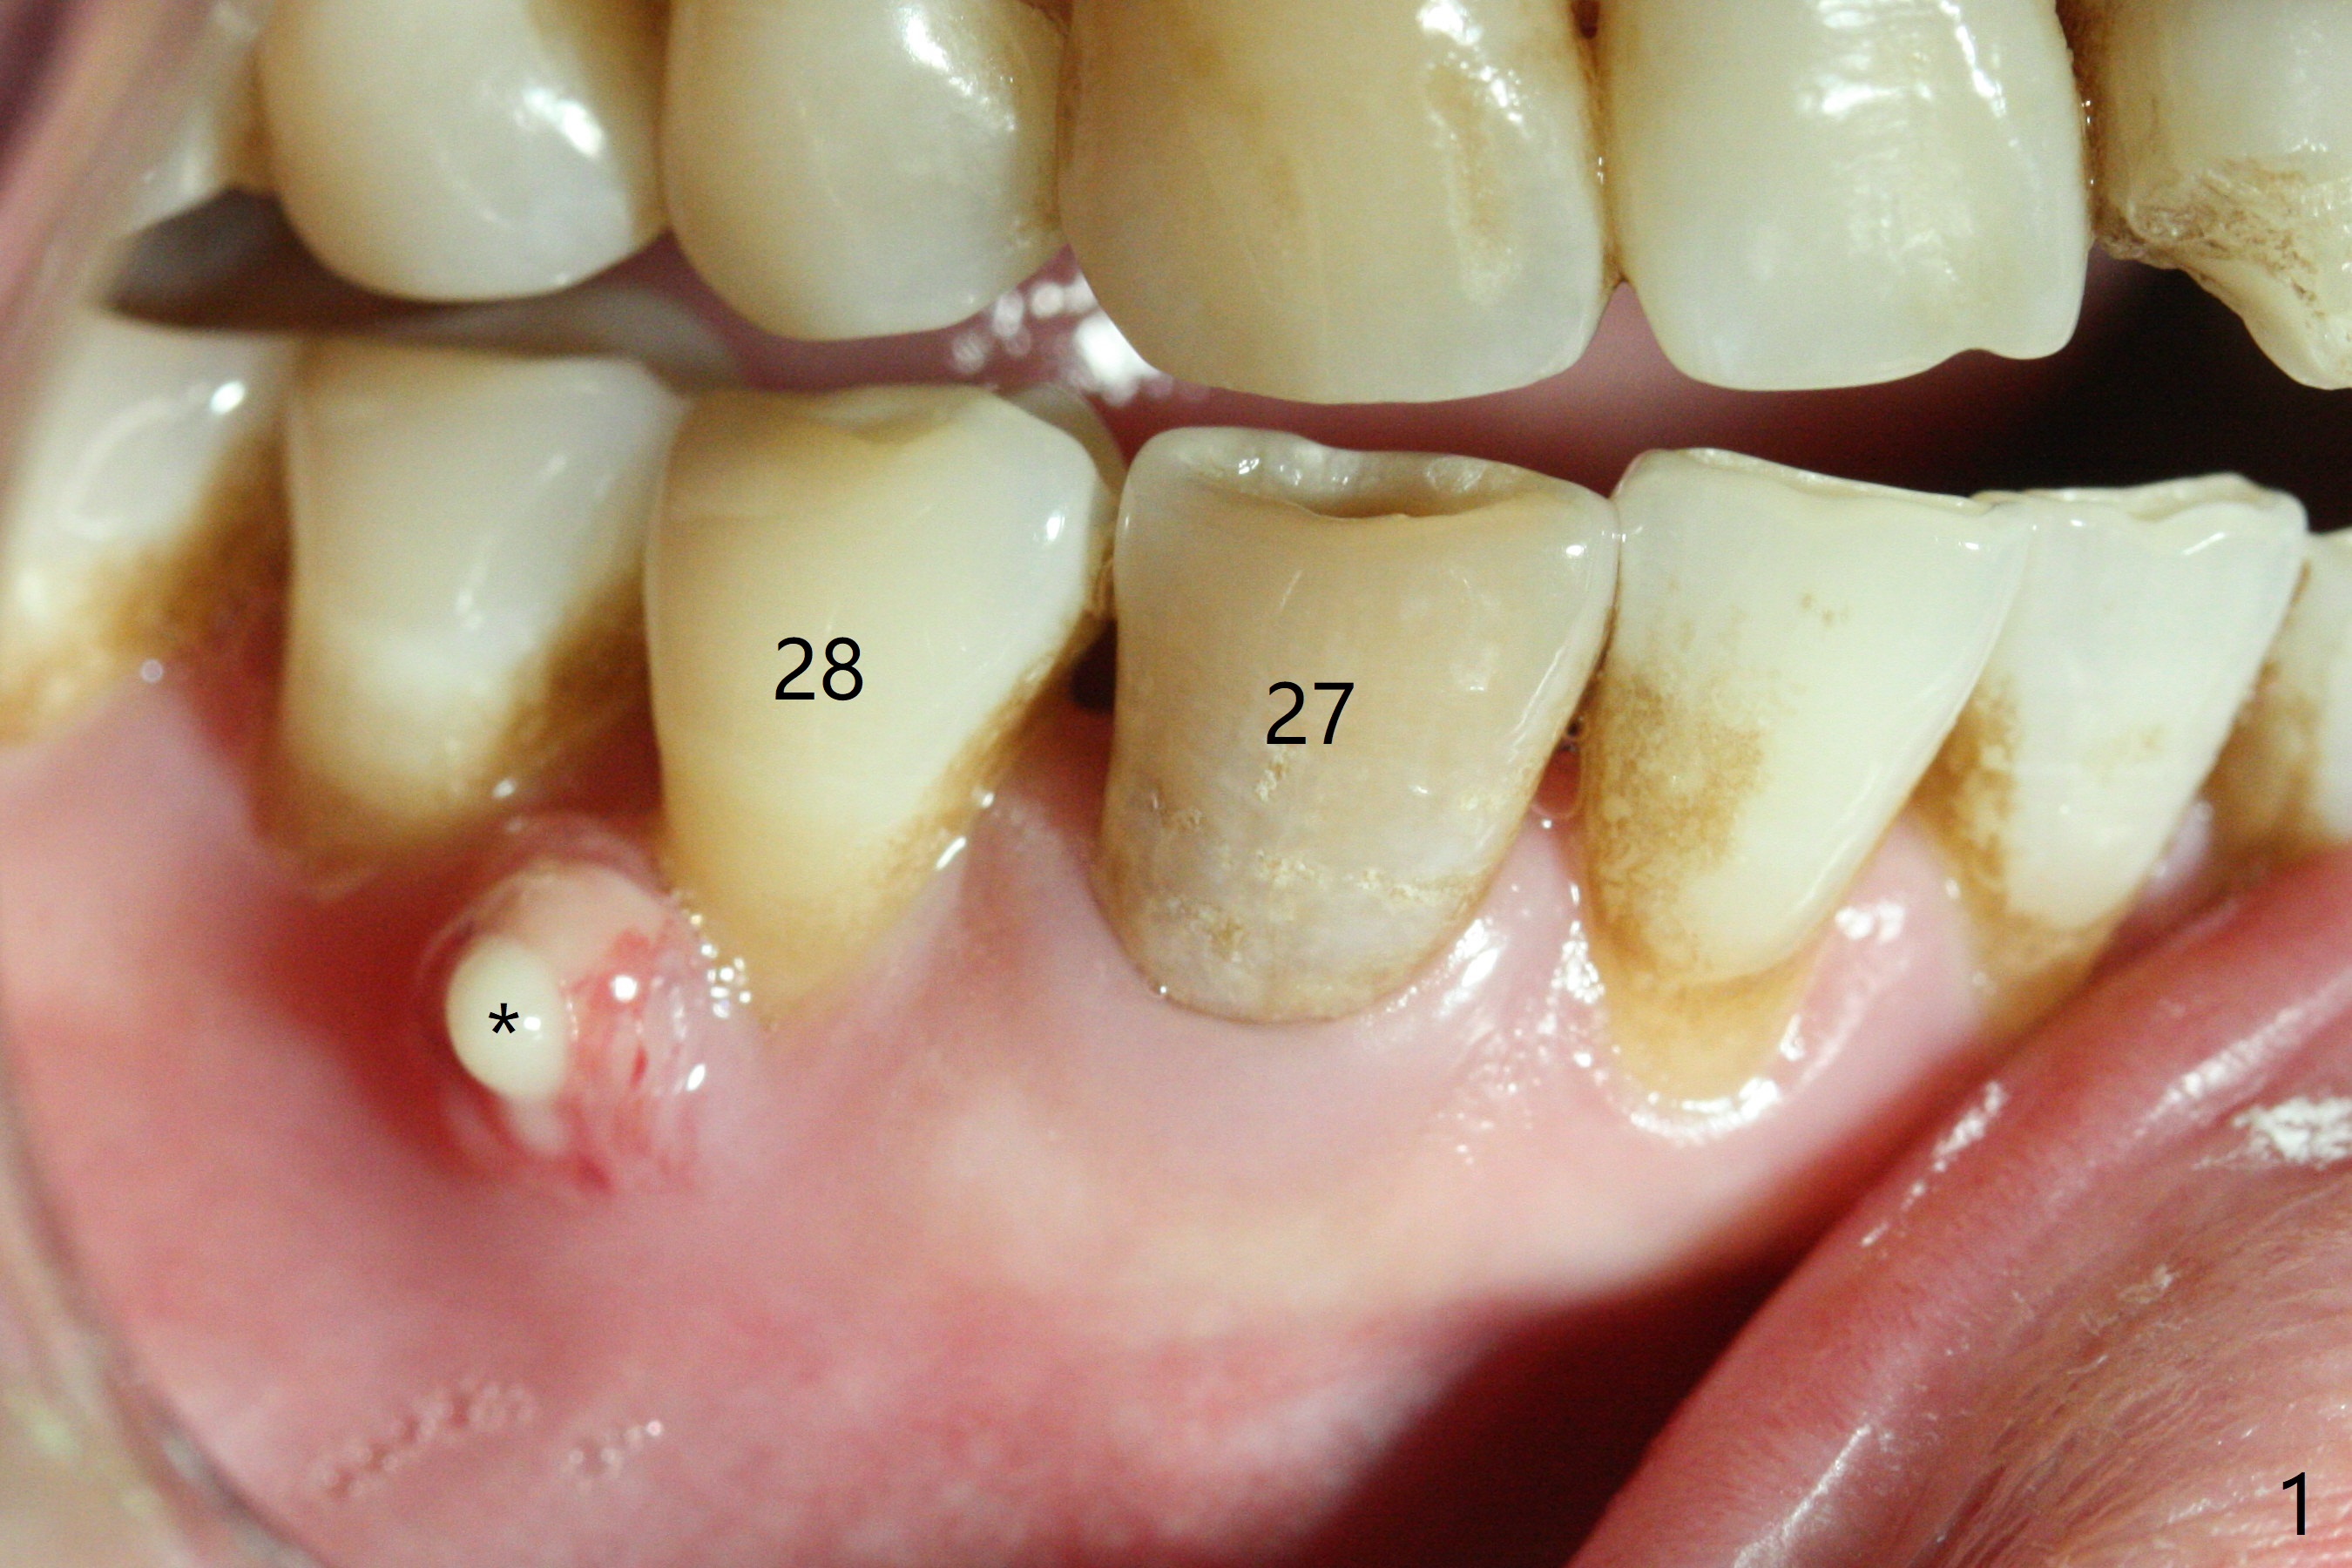

A 47-year-old woman with autoimmune hepatitis has a fistula distal to the tooth #28 (Fig.1). Periapical radiolucency appears to involve the teeth #27 and 28. Which is the infected tooth? Treatment plan?